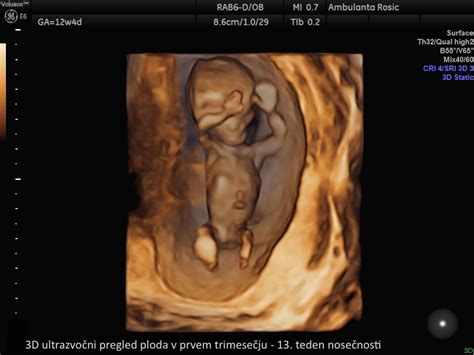

Zgodnji razvoj ploda: Kaj lahko pričakujemo med 11. in 14. tednom nosečnosti?

Ultrazvočno merjenje nuhalne svetline je časovno zelo specifično in ga je nujno opraviti med 11. tednom nosečnosti (ko plod meri 45 mm od glave do trtice) in 14. tednom nosečnosti (ko plod meri 84 mm). Ta časovni okvir je ključen, saj se v njem optimalno izmeri debelina tekočine pod kožo na vratu ploda, ki je eden izmed ključnih kazalnikov za morebitne kromosomske nepravilnosti. Pregled se običajno izvaja preko trebuha nosečnice (transabdominalni ultrazvok), redkeje pa je potrebna uporaba vaginalne sonde (transvaginalni ultrazvok). Pred posegom je nosečnico vljudno prosimo, da popolnoma izprazni mehur, kar omogoča boljšo vidljivost in natančnejše meritve.

Med samim pregledom natančno izmerimo več ključnih parametrov. Frekvenca srčnega utripa ploda je eden prvih pokazateljev njegove vitalnosti. Sledijo meritve velikosti ploda od vrha glave do trtice (crown-rump length - CRL) in premer glavice. Posebno pozornost namenimo prisotnosti nosne kosti, ki je pri plodu z Downovim sindromom pogosto odsotna ali manj razvita. Ocenimo obliko glavice in razvoj možganskih struktur, preverimo prisotnost srca, želodčka in sečnega mehurja ter se prepričamo, da je trebušna stena v celoti prekrita z kožo. Podrobno pregledamo tudi dolge kosti zgornjih in spodnjih okončin ter hrbtenico. V določenih primerih, z okoli 60 % gotovostjo, lahko že v tej zgodnji fazi nosečnosti napovemo spol otroka, vendar natančna ugotovitev spola običajno poteka v kasnejših tednih. V primeru, ko je razlika med pričakovano velikostjo ploda glede na termin poroda in dejansko izmerjeno velikostjo večja od sedmih dni, se za izračun tveganja za Downov sindrom uporabi ultrazvočno izmerjena gestacijska starost.

Pogosto se poraja vprašanje, ali je smiselno opraviti pregled nuhalne svetline, če se že odločamo za NIFTY test. Odgovor je odločen DA. Hkrati z meritvijo nuhalne svetline se namreč opravi tudi natančna zgodnja morfologija ploda in izračuna tveganje za nastanek preeklampsije. Zgodnja morfologija ploda je sestavni del pregleda nuhalne svetline in vključuje oceno zgodnjega razvoja srca in glavice, prisotnost želodca in sečnega mehurja, razvoj okončin, hrbtenice in trebušne pregrade, zaprtost trebušne stene ter razvoj popkovnice. Kvaliteta tega pregleda je v veliki meri odvisna od izurjenosti izvajalca.